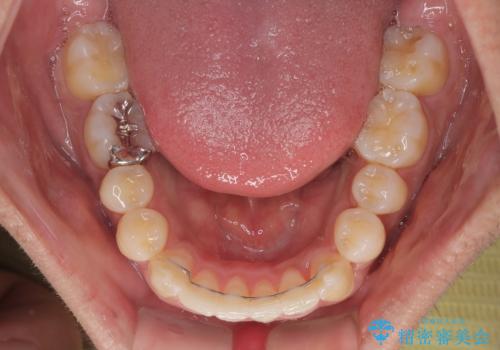

気になる前歯のデコボコと八重歯 ワイヤー矯正ですっきりと

- 前歯のデコボコや八重歯を気にして来院された患者様です。

他院でワイヤー矯正を行うつもりでいらっしゃったそうですが、通院が難しくなったとのことで当院での治療を希望されて来院されました。

上下ともに歯列幅が狭く、その影響でデコボコになっていたため、ワイヤー装置を用いて歯列を側方に拡大しながら、デコボコを解消していくこととしました。

矯正治療後には気になっていた前歯をセラミッククラウンにし、自然な口元に仕上げることができました。